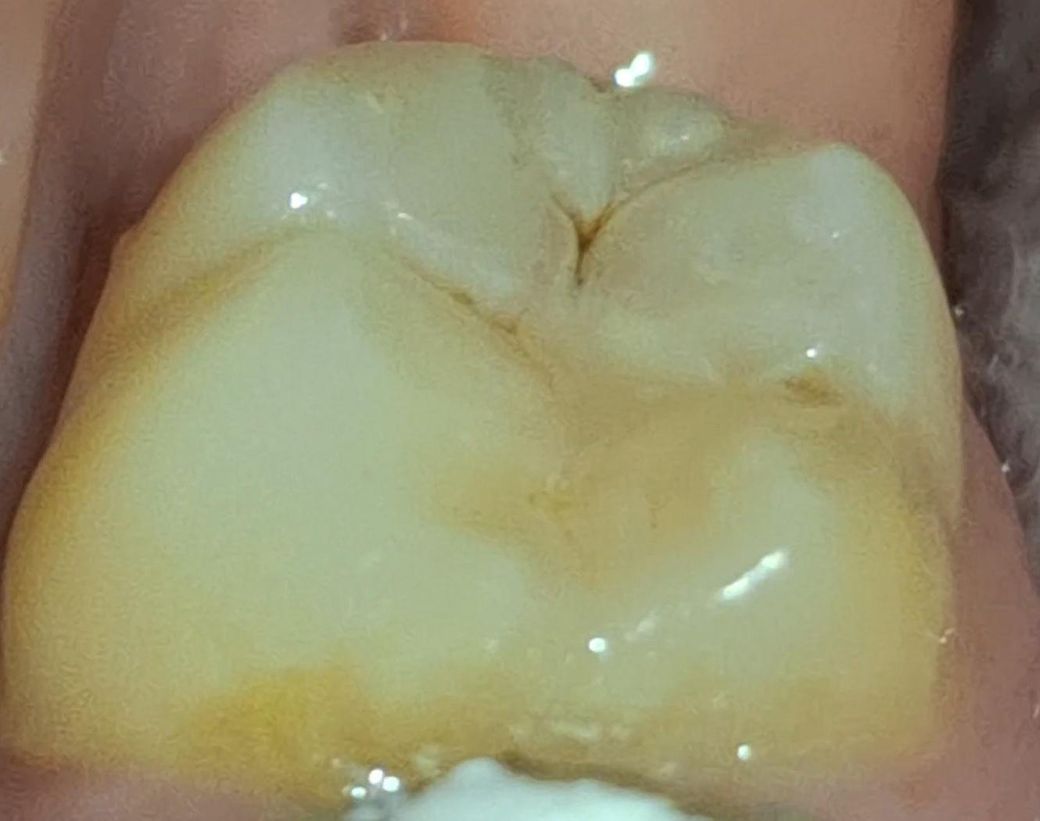

레진 치료 다시 받아야 할까요? 레진 살짝 벗겨졋는데 충치같은게 보여요 ㅠ

7월 초에 레진한 곳 옆부분이 조금 벗겨졌는데 .. 충치같은 게 보여서요.

빨간 동그라미 부분 첨이랑 달리 조금 벗겨졌는데.. 검갈색에 자국이 보여서요.

사진상으로는 잘 안보여도 실제로 보면 더 잘보여요 ㅠㅠ

제가 궁금한 부분은 레진 벗겨진 곳에 갈색 자국이 있어도 되는건가요? 저것도 정지우식이라서 그냥 레진으로 덮으신걸까요?

사진에 상에 보이는 충치는 치료를 해야될것같으니 치과에 가셔서 검진후 치료를 받으시는게 좋을것같습니다.

사진으로 봤을 떄에는 정지우식같아 보이기는 합니다만 벗겨졌다면 재치료 받으시면 됩니다.

사진으로 봤을 경우에는 치아에 홈이 생긴 것으로 보입니다. 치아에 홈이 생기게 되면 대부의 이물질이 들어가게 되어 충치가 더 커질수 있습니다. 이런 경우 홈이 있는 부분을 메꿔주는 것이 좋을 수 있습니다.

자세한 확인을 위해서 치과에서 진료를 받아보는 것을 권유드립니다.

빨간원 안쪽도 그렇고 그 옆쪽도 아직 충치가 있어보입니다 치과가서 해당 부위 전반적으로 다시 봐달라고하세요